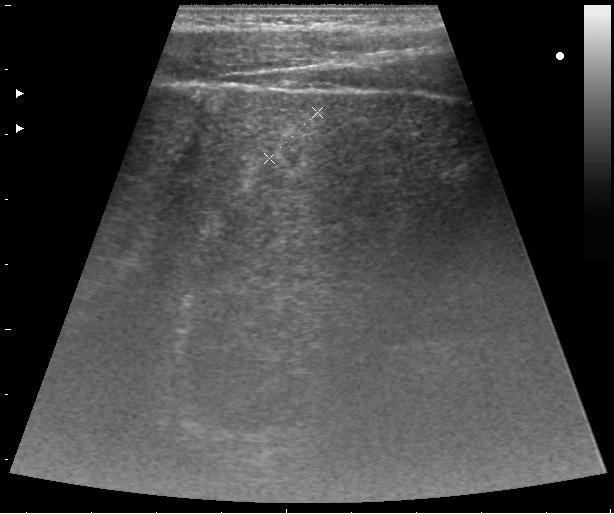

сегодня был селезёночный день.

>желтой стрелкой - это левый надпочечник?

Похоже.

Он обычно располагается больше кнутри от верхнего полюса почки и может досигать ее ворот.

Надежнее визуализировать ЛН из позиции, которую я показывал в известной Вам теме.